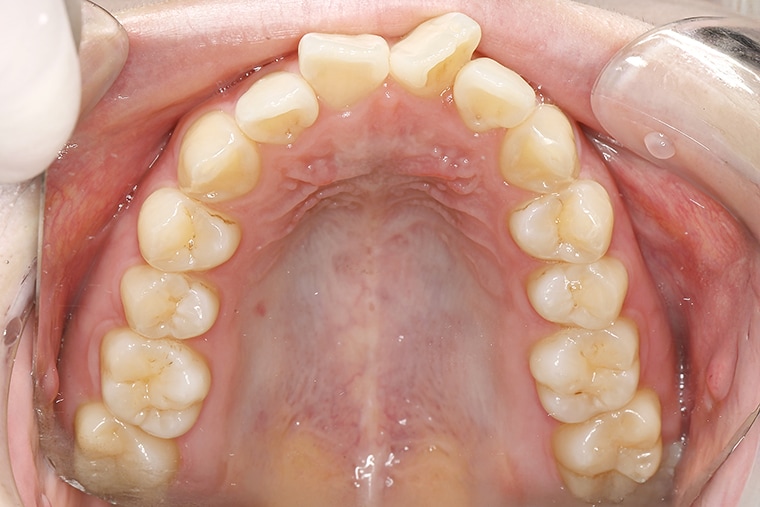

25歳男性ガタガタな歯のマウスピース矯正-矯正期間6ヶ月

- 治療費用

- 968,000円(税込)

- 治療期間

- 6ヶ月

- 性別

- 男性

- 年齢

- 25歳

- 抜歯

- 無し

- 治療方法

- マウスピース矯正(インビザラインModerate)による治療方法

- 治療リスク

- 1日22時間の装着時間を守らないと治療期間が遅くなり、歯並びの質が悪くなります

患者さまの声

歯の噛み合わせが一番気になっていたのでマウスピース矯正を始めました。

最初はちゃんと治るか不安でしたが、近所で一番大きい医院だったので安心できました。

約6ヶ月の治療で気になっていた部分はしっかり改善され、噛み合わせも良くなり満足しています。